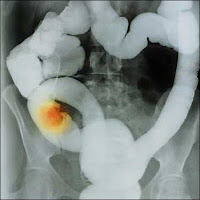

Un ejemplo de cáncer de Reishi de lucha contra el potencial ocurrido en el verano de 1986. A 39 años de edad, La mujer japonesa se acercó a la Dra. Fukumi Morishige, MD, Ph.D, un japonés de renombre cirujano y miembro del Instituto Linus Pauling de Ciencia y Medicina, para ayudar en el tratamiento de su cáncer de pulmón. Era un caso complicado, y que había

sido denegada una operación por varios hospitales. Hopeless, regresó a su casa donde encontró a su marido había recogido Reishi en los bosques. El cocido de setas y se lo dio a beber como un té.

Mientras esto sucedía, le pidió el Dr. Morishige hacer algo por su cáncer, independientementede su fase muy avanzada. De lo que fue e

vidente, seis meses antes, fue sorprendido Morishige cuando no encontró un aumento en la hinchazón. Luego la miró rayos-X. Algo no estaba bien: su tumor mostró que sólo una huella en la radiografía.Cuando ella le dijo que había estado bebiendo Reishi té, Morishige operado con gran curiosidad. Él estaba "asombrado" de encontrar sólo el tejido cicatrizal, yAunque las células cancerosas se mantuvo, ahora eran benignos.

Ese fue el impulso para el Dr. Morishige para iniciar sus estudios de Reishi como tratamiento para el cáncer de especialmente los casos, dado por imposible. Dr. Morishige ahora cree que el Reishi es también una prevención eficaz del cáncer. Los constituyentes activos anti-cáncer en el Reishi son llamados Beta-D-glucano.